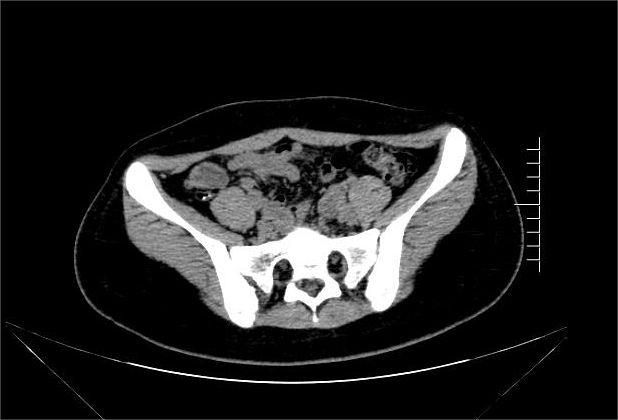

患儿王某,14岁,因“反复腹痛1年,加重3天”入院,入院完善腹部CT提示“阑尾体积增大,局部壁稍模糊,内见点状致密灶,右下腹多发淋巴结”,根据影像诊断为:阑尾粪石,阑尾炎。